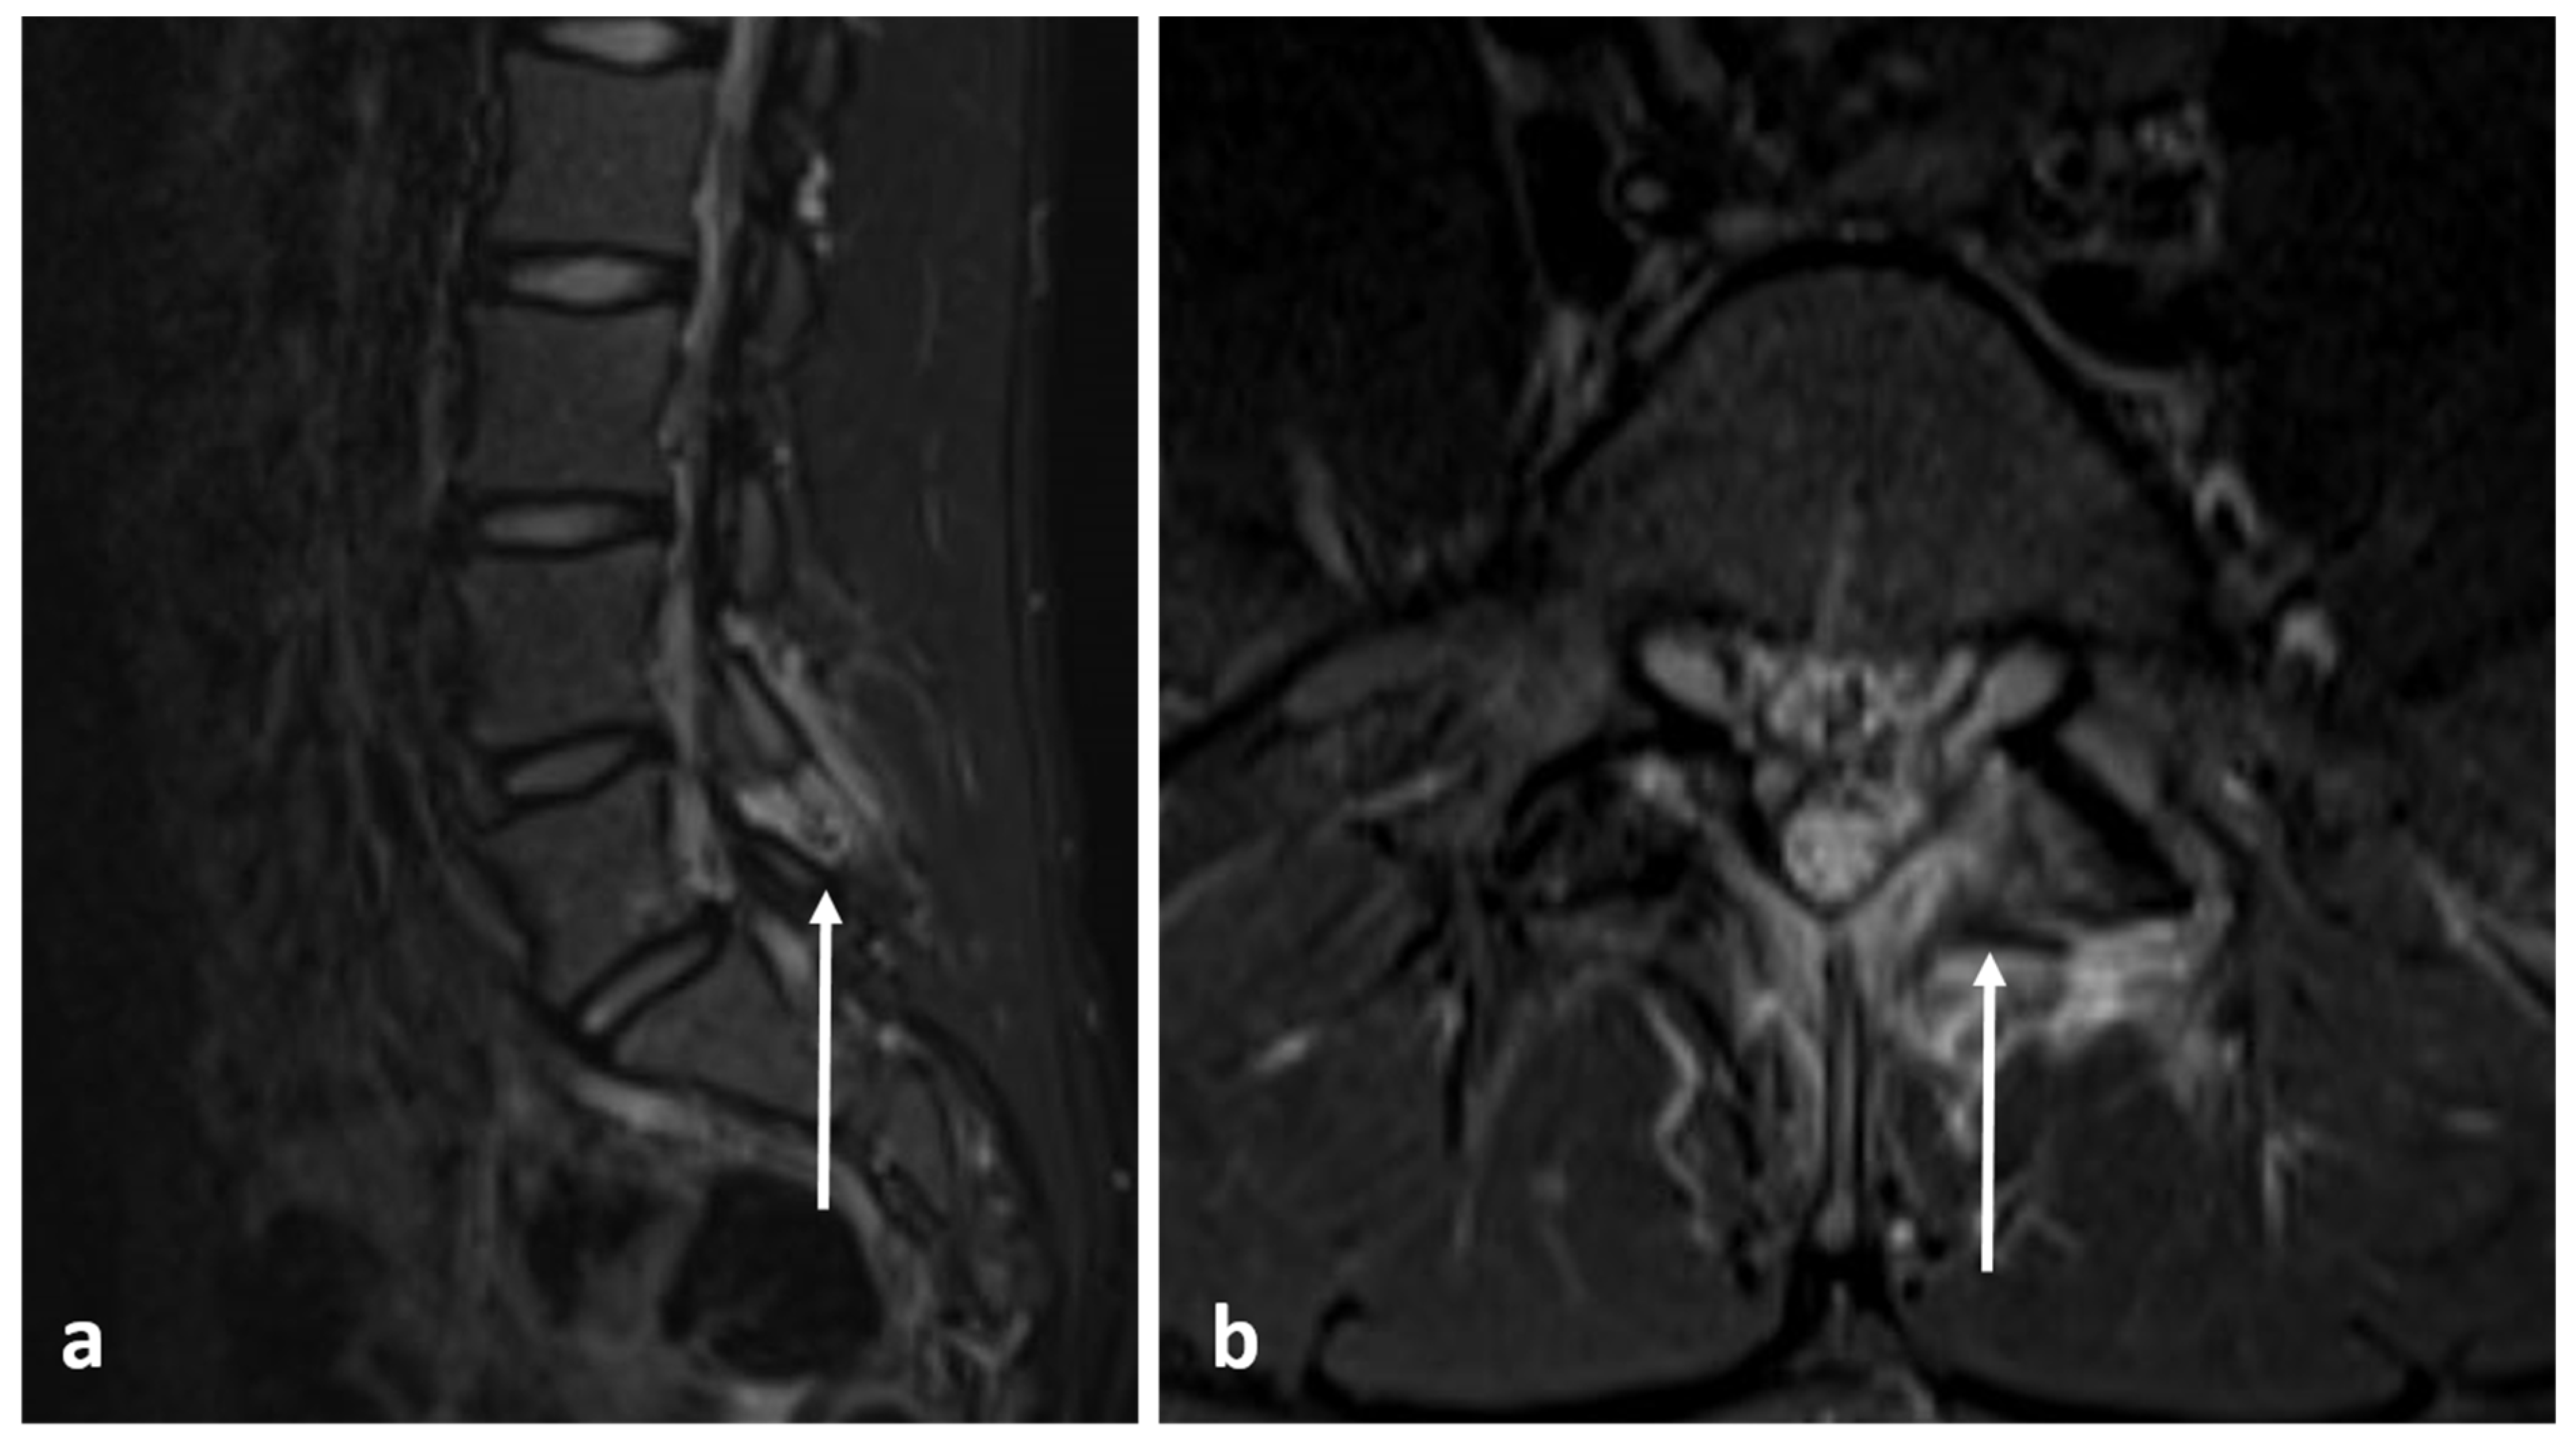

| Aneurysmal bone cyst | Expansile lytic lesion with internal bone septations. | Fluid—fluid levels within the cysts, high T1 signal within layering fluid content due to haemorrhage. |